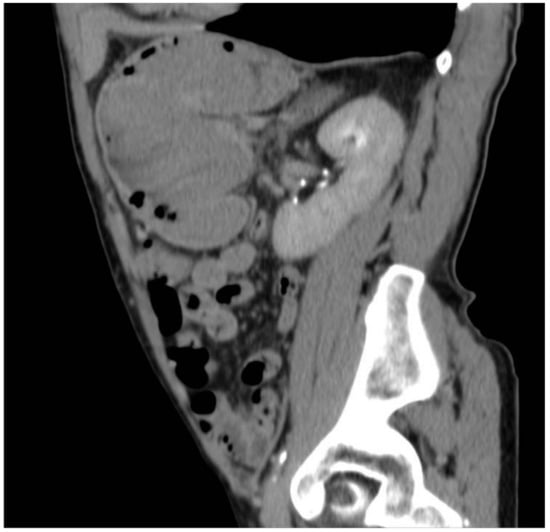

2. Case Report